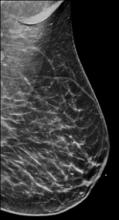

Coronavirus (COVID-19) | May 11, 2021

Yael Eshet, M.D., MSc, a diagnostic radiology specialist at Sheba Medical Center in Israel, was the lead author on a recent study that showed COVID-19 (SARS-CoV-2) vaccine adenopathy can persist more than 6 weeks. This swelling of lymph nodes is similar to what is seen cancer and infections and the new findings show it can last longer than 7-10 weeks. The current recommended time people should delay medical imaging is 6 weeks after receiving a COVID vaccine to avoid a misdiagnosis,[2] but this new study shows there is increased inflammation shown on PET-CT imaging for much longer.

These were the findings in the Radiology published study "Prevalence of Increased FDG PET/CT Axillary Lymph Node Uptake Beyond 6 Weeks after mRNA COVID-19 Vaccination."[1]

Researchers using fluorodeoxyglucose (FDG)-positron emission tomography (PET) have found increased FDG uptake in the lymph nodes of patients 7-10 weeks past their second mRNA-based Pfizer-BioNTech COVID-19 vaccination. This new information indicates a persistent immune response that could be mistaken on imaging exams for serious conditions like lymphoma over a much longer period of time.

Recent recommendations for post-vaccine lymphadenopathy advise scheduling routine imaging, such as screening mammography, before, or at least 6 weeks after, the final vaccination dose to eliminate false positive results. However, this new research showed that avid axillary lymph node uptake was present beyond 6 weeks after the second vaccination in more than 29% of the patients in the study cohort.

The authors stated “This study shows that avid axillary lymph node uptake on FDG PET/CT can be detected in more than a quarter of our patient population even beyond 6 weeks after the second dose of the mRNA-based COVID-19 vaccination. Compared to a previous study showing normalization of FDG uptake within 40 days of receiving an inactivated H1N1 influenza vaccine, we found uptake persistence even at 70 days. Physicians should be aware of this potential pitfall.”

Some images in this video are from another Radiology study, which showed PET tracer uptake at the COVID vaccine injection site and other examples of axillary adenopathy.[3]